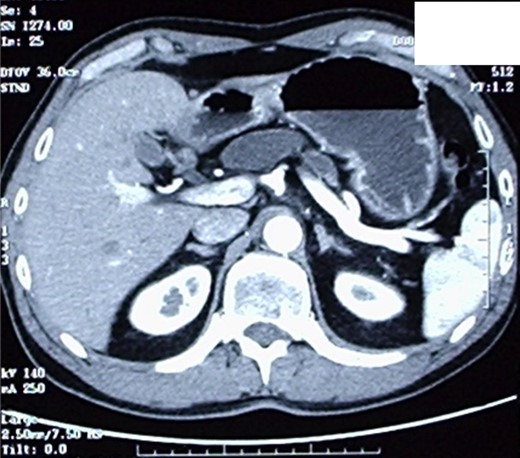

The patient therefore underwent a computed tomography (CT) scan (Figs 1 and 2) that revealed ‘a thickened duodenal wall and a sero-cystic lesion of the pancreatic head without contrast-enhancement, which compressed the duodenal lumen and caused a dilation of the Wirsung duct’. The liver, the gallbladder and the extrahepatic biliary tree were normal. No lymphadenopathy was found.

Another image of the CT scan, showing a sero-cystic lesion of the pancreatic head.